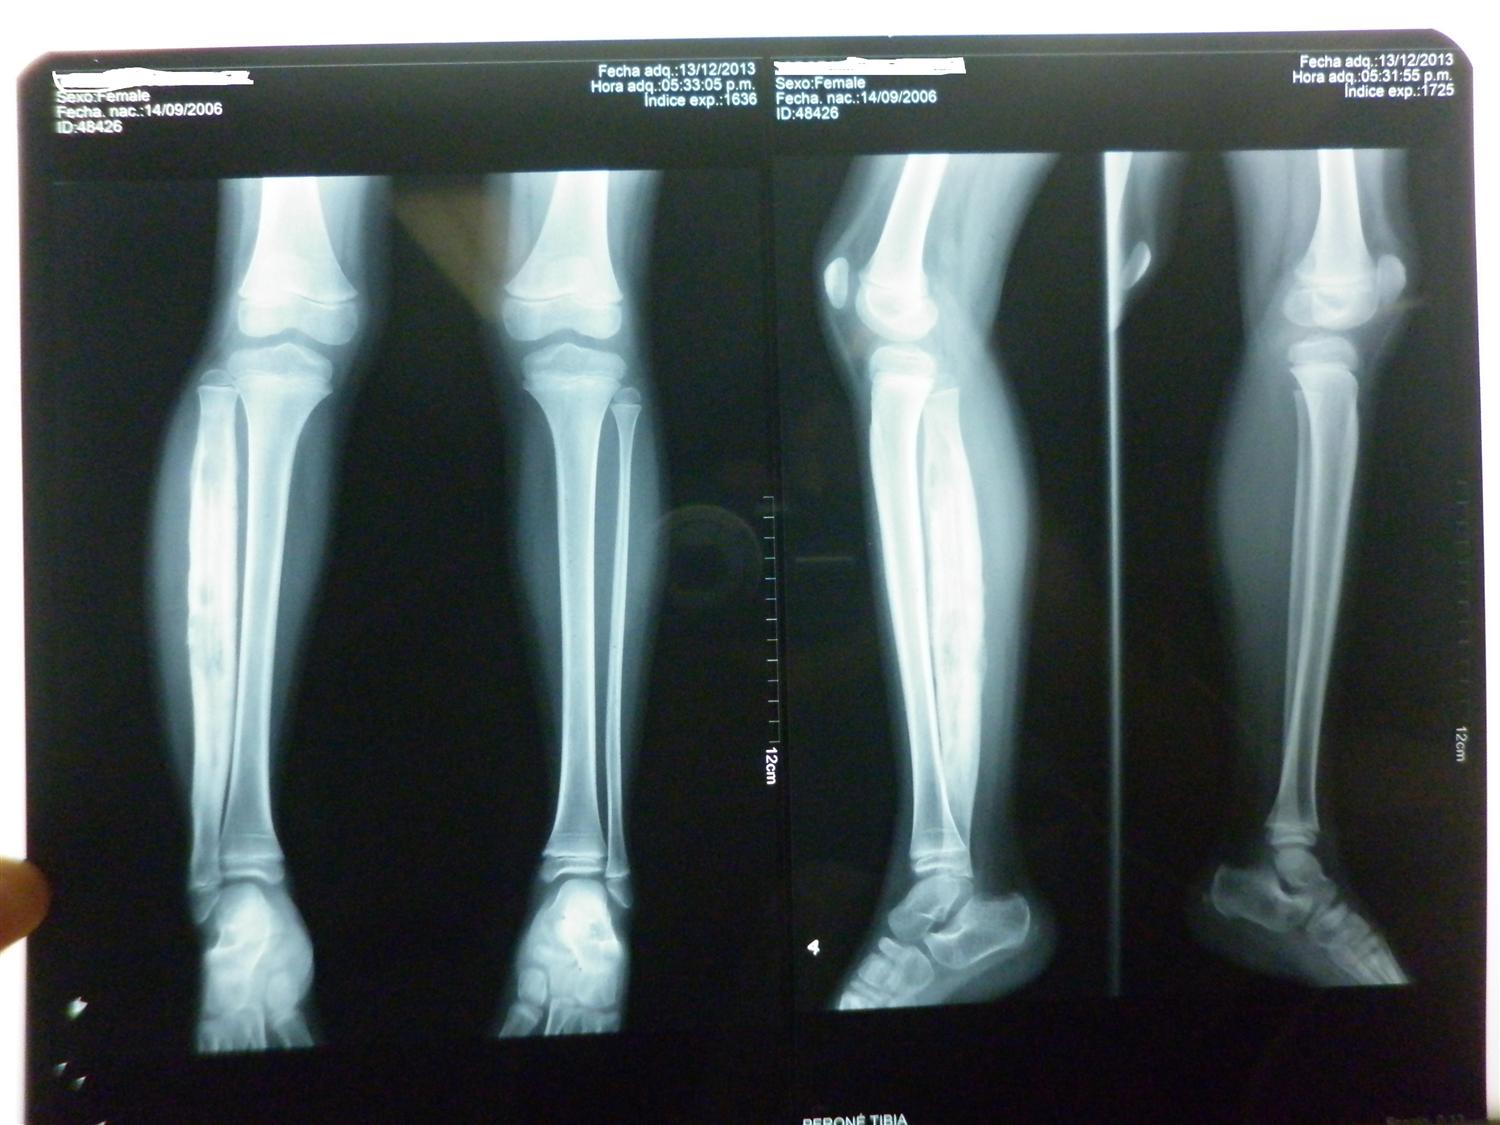

Tibial osteomyelitis, in child aged one year. Sagittal T2 weighted MR Osteomyelitis Symptoms In Child However, each child may experience symptoms differently. Osteomyelitis can have a sudden onset, a slow and mild onset or may be a chronic problem, depending on the source of the infection. Symptoms of osteomyelitis vary depending on the type and cause. The following are the most common symptoms of osteomyelitis. While symptoms can vary from child to child, the most. Osteomyelitis Symptoms In Child.